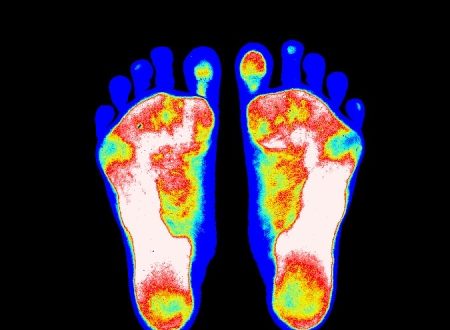

インソール専門外来

足は生活の中でカラダを支えてくれる土台です。生涯を通して足のトラブルを抱える方への問題解決に協力いたします。- 外反母趾、浮き指、足が痛い

- 靴が合わない、選び方がわからない

- 専門家よるインソール治療